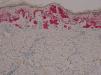

Presentamos el caso de un paciente caucásico de 42 años de edad, con un melanoma estadio iv, diagnosticado hacía 6 años de melanoma en el brazo derecho con ganglio centinela positivo, al que se le realizó linfadenectomía axilar derecha y tratamiento posterior con interferón. En controles posteriores, 6 años después, se objetivaron 2 nódulos pulmonares y lesiones óseas metastásicas en C5, D11 y ambas palas ilíacas y sacro, por lo que al detectarse la mutación BRAF V600E se inició tratamiento con vemurafenib 960mg cada 12h. Dos meses después de iniciar el tratamiento se objetivó una lesión papular en el muslo izquierdo, que no estaba presente en la revisión anterior un mes antes, de 10×8mm, cupuliforme, del color de la piel, asintomática, que había ido creciendo (fig. 1). Se le realizó una biopsia-extirpación de la lesión con el diagnóstico de sospecha de queratosis actínica hipertrófica, siendo la lesión extirpada en su totalidad. La evaluación histológica mostró una proliferación de melanocitos en la epidermis y en la dermis papilar, con discreta atipia arquitectural (fig. 2). Los melanocitos se agrupaban formando nidos en la epidermis y en la dermis papilar, con discreto pleomorfismo nuclear. Se solicitó estudio inmunohistoquímico con Melan-A y HMB-45 que mostró una proliferación de melanocitos en la capa basal de la epidermis con focos de melanocitos en capas más altas de la epidermis (fig. 3). Todos estos hallazgos son compatibles con un nevus atípico.